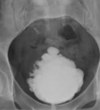

13

Q

A

Think schistosomiasis infection and be suspicious of squamous cell carcinoma of the bladder

Note: Any irregular bladder/ureteral calcifications should raise suspicion for squamous cell carcinoma.

Bladder calcification should make you think schistosomiasis infection and worry about squamous cell carcinoma of the bladder Note: Any irregular bladder/ureteral calcifications should raise suspicion for squamous cell carcinoma.